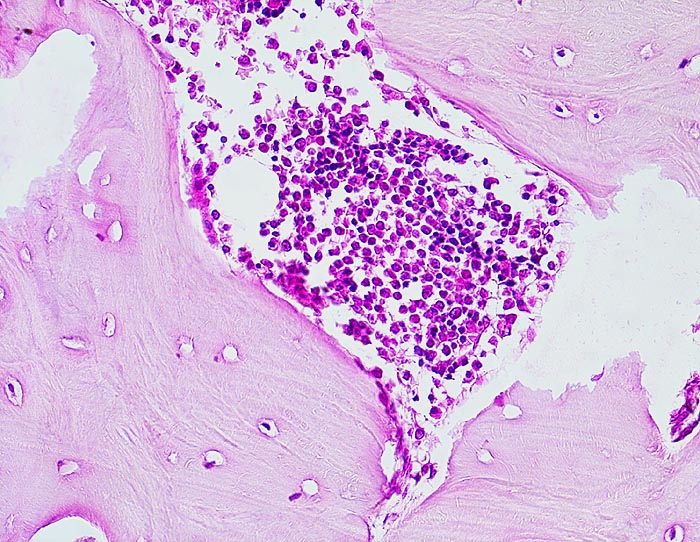

Da Adenokarzinome neben der Prostata in fast allen Organen vorkommenen, ist die Differentialdiagnose im HE Schnitt bei Nachweis einer Knochenmetastase eines Adenokarzinoms sehr breit. Die immunhistochemische Positivität der Tumorzellen für prostataspezifisches Antigen (PSA) spricht für eine Primärtumorherkunft aus der Prostata. Prostatakarzinome bilden typischerweise osteoplastische Knochenmetastasen. Die Knochenbildung erfolgt via Cytokine und Wachstumsfaktoren, die von den Tumorzellen gebildet werden (z.B. TGF-beta), durch Stimulation der Osteoblasten, wahrscheinlich bei gleichzeitiger lokaler Reduktion der Osteoklastenaktivität (RANK/RANKL/OPG-System). Die Stimulation von Osteoblasten führt zu einer vermehrten appositionellen Osteoidneubildung entlang vorhandener Trabekel mit nachfolgender Mineralisierung. Durch fortgeschrittene Knochenneubildung kommt es zu einer vollständigen Ummauerung grösserer Tumorareale, welche durch die verminderte Blutzufuhr nekrotisch werden. Vielfach lassen sich histologisch osteoplastische und osteolytische Anteile nachweisen. Immunhistochemisch lässt sich in den Metastasen oft Prostata spezifisches Antigen nachweisen (> 5342).

Morphologische Merkmale:

• Fehlen von blutbildendem Knochenmark.

• Infiltration des Knochemarks durch kleine dichtgepackte, kribriforme Strukturen ausbildende Karzinomdrüsen.

• Osteplastische Metastase: Faserknochenneubildung zwischen vorbestehenden Trabekeln.

• Anhand der Histologie kann lediglich die Diagnose einer Metastase eines Adenokarzinoms gestellt werden. Kleine, solide Verbände bildende Tumordrüsen und grosse Nukleolen sind typisch für ein Prostatakarzinom. Die Diagnose muss aber durch den Vergleich mit der Morphologie des Primärtumors oder eine Immunhistochemische Untersuchung (PSA, PSAP) bestätigt werden.